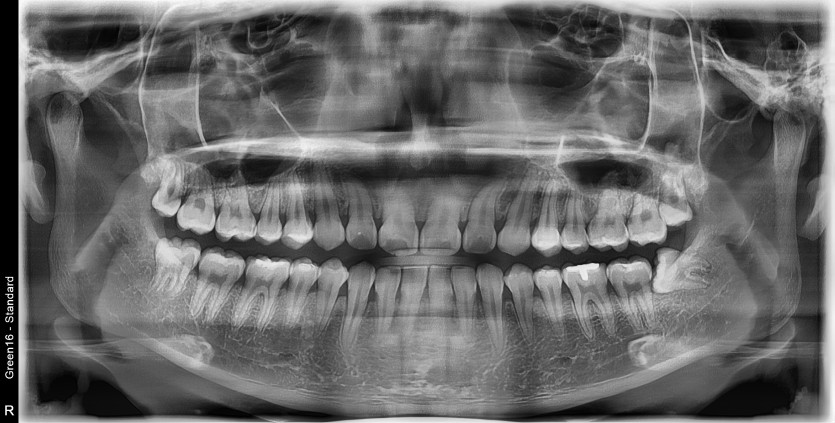

#28,38 사랑니 발치

구강 외과 전문의가 당일 발치했습니다.